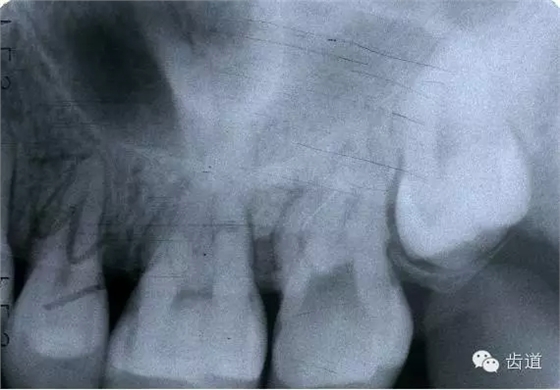

左上5牙頸部側(cè)穿

開(kāi)髓時(shí)鉆針進(jìn)入方向與根管走行方向不一致,鉆針需改變方向時(shí)。

牙長(zhǎng)軸傾斜,在傾斜方向的髓腔壁易穿孔